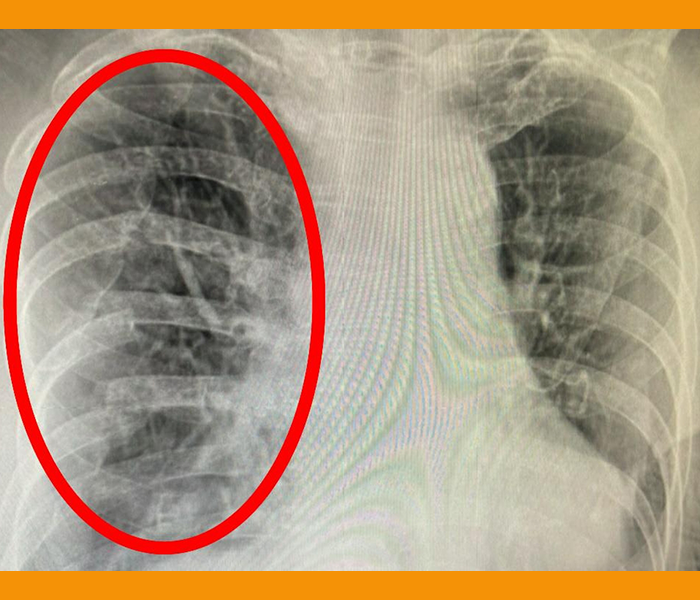

6. 갈비뼈 골절

갈비뼈는 척추와 다르게 얇고 길며 상대적으로 쉽게 손상될 수 있습니다. 넘어지거나 외부충격을 받은 경우, 또는 기침을 하다가도 골절이 발생할 수 있으며, 이로 인해 오른쪽 옆구리에 통증이 생길 수 있습니다. 갈비뼈가 골절되면 깊게 숨을 들이마실 때나 기침을 할 때 통증이 심해지는 경향이 있습니다.

갈비뼈 골절은 대개 자연치유가 가능하나, 심한 경우 흉부외과에서 추가적인 진료와 치료가 필요할 수 있습니다. 통증을 완화하기 위해 진통제를 사용하고, 휴식을 취하면서 골절 부위에 무리가 가지 않도록 주의해야 합니다.